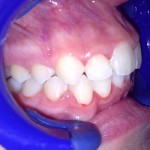

Este é um caso mais simples de se fazer e com um valor (custo-benefício) bastante cómodo.São somente 4 implantes na arcada inferior suportando uma barra sobre a qual será transferido em parte o esforço mastigatório. É confeccionada em RESINA como uma prótese total convencional.